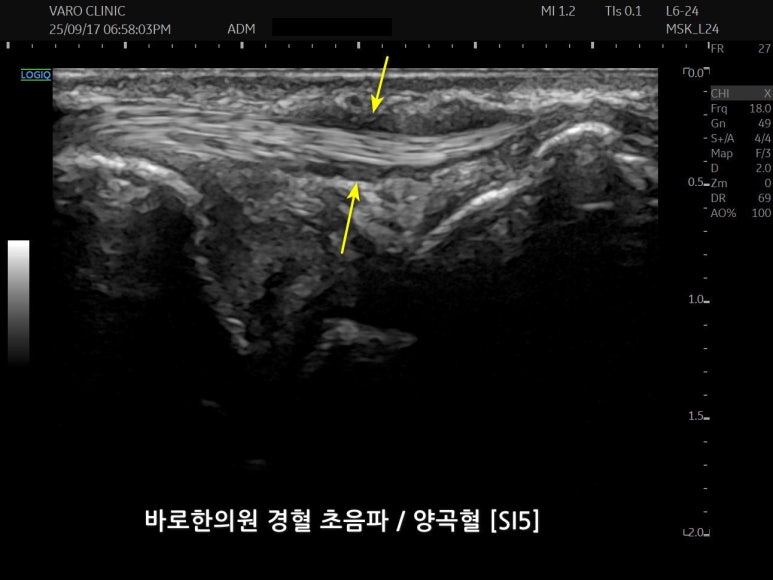

저는 대한한의영상학회 교육이사로

GE 초음파의 1억 원대 최상위 기종을 사용하는

누구보다 초음파에 진심인 사람입니다.

문제가 있는 혈자리를

초음파로 보면서

약침 주사를 시술합니다.